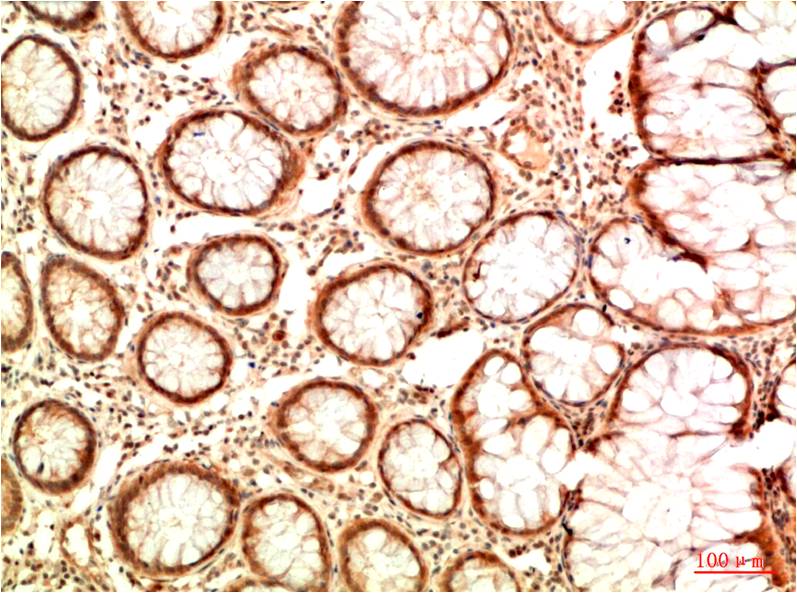

Acetyl P53(K382) Mouse Monoclonal Antibody(5H10)

Applications :IHC

| Recommended dilutions: | IHC: 1:100-200 |

| Specificity: | The Acetyl P53(K382) Mouse Monoclonal Antibody can detects endogenous Acetyl P53(K382) proteins. |